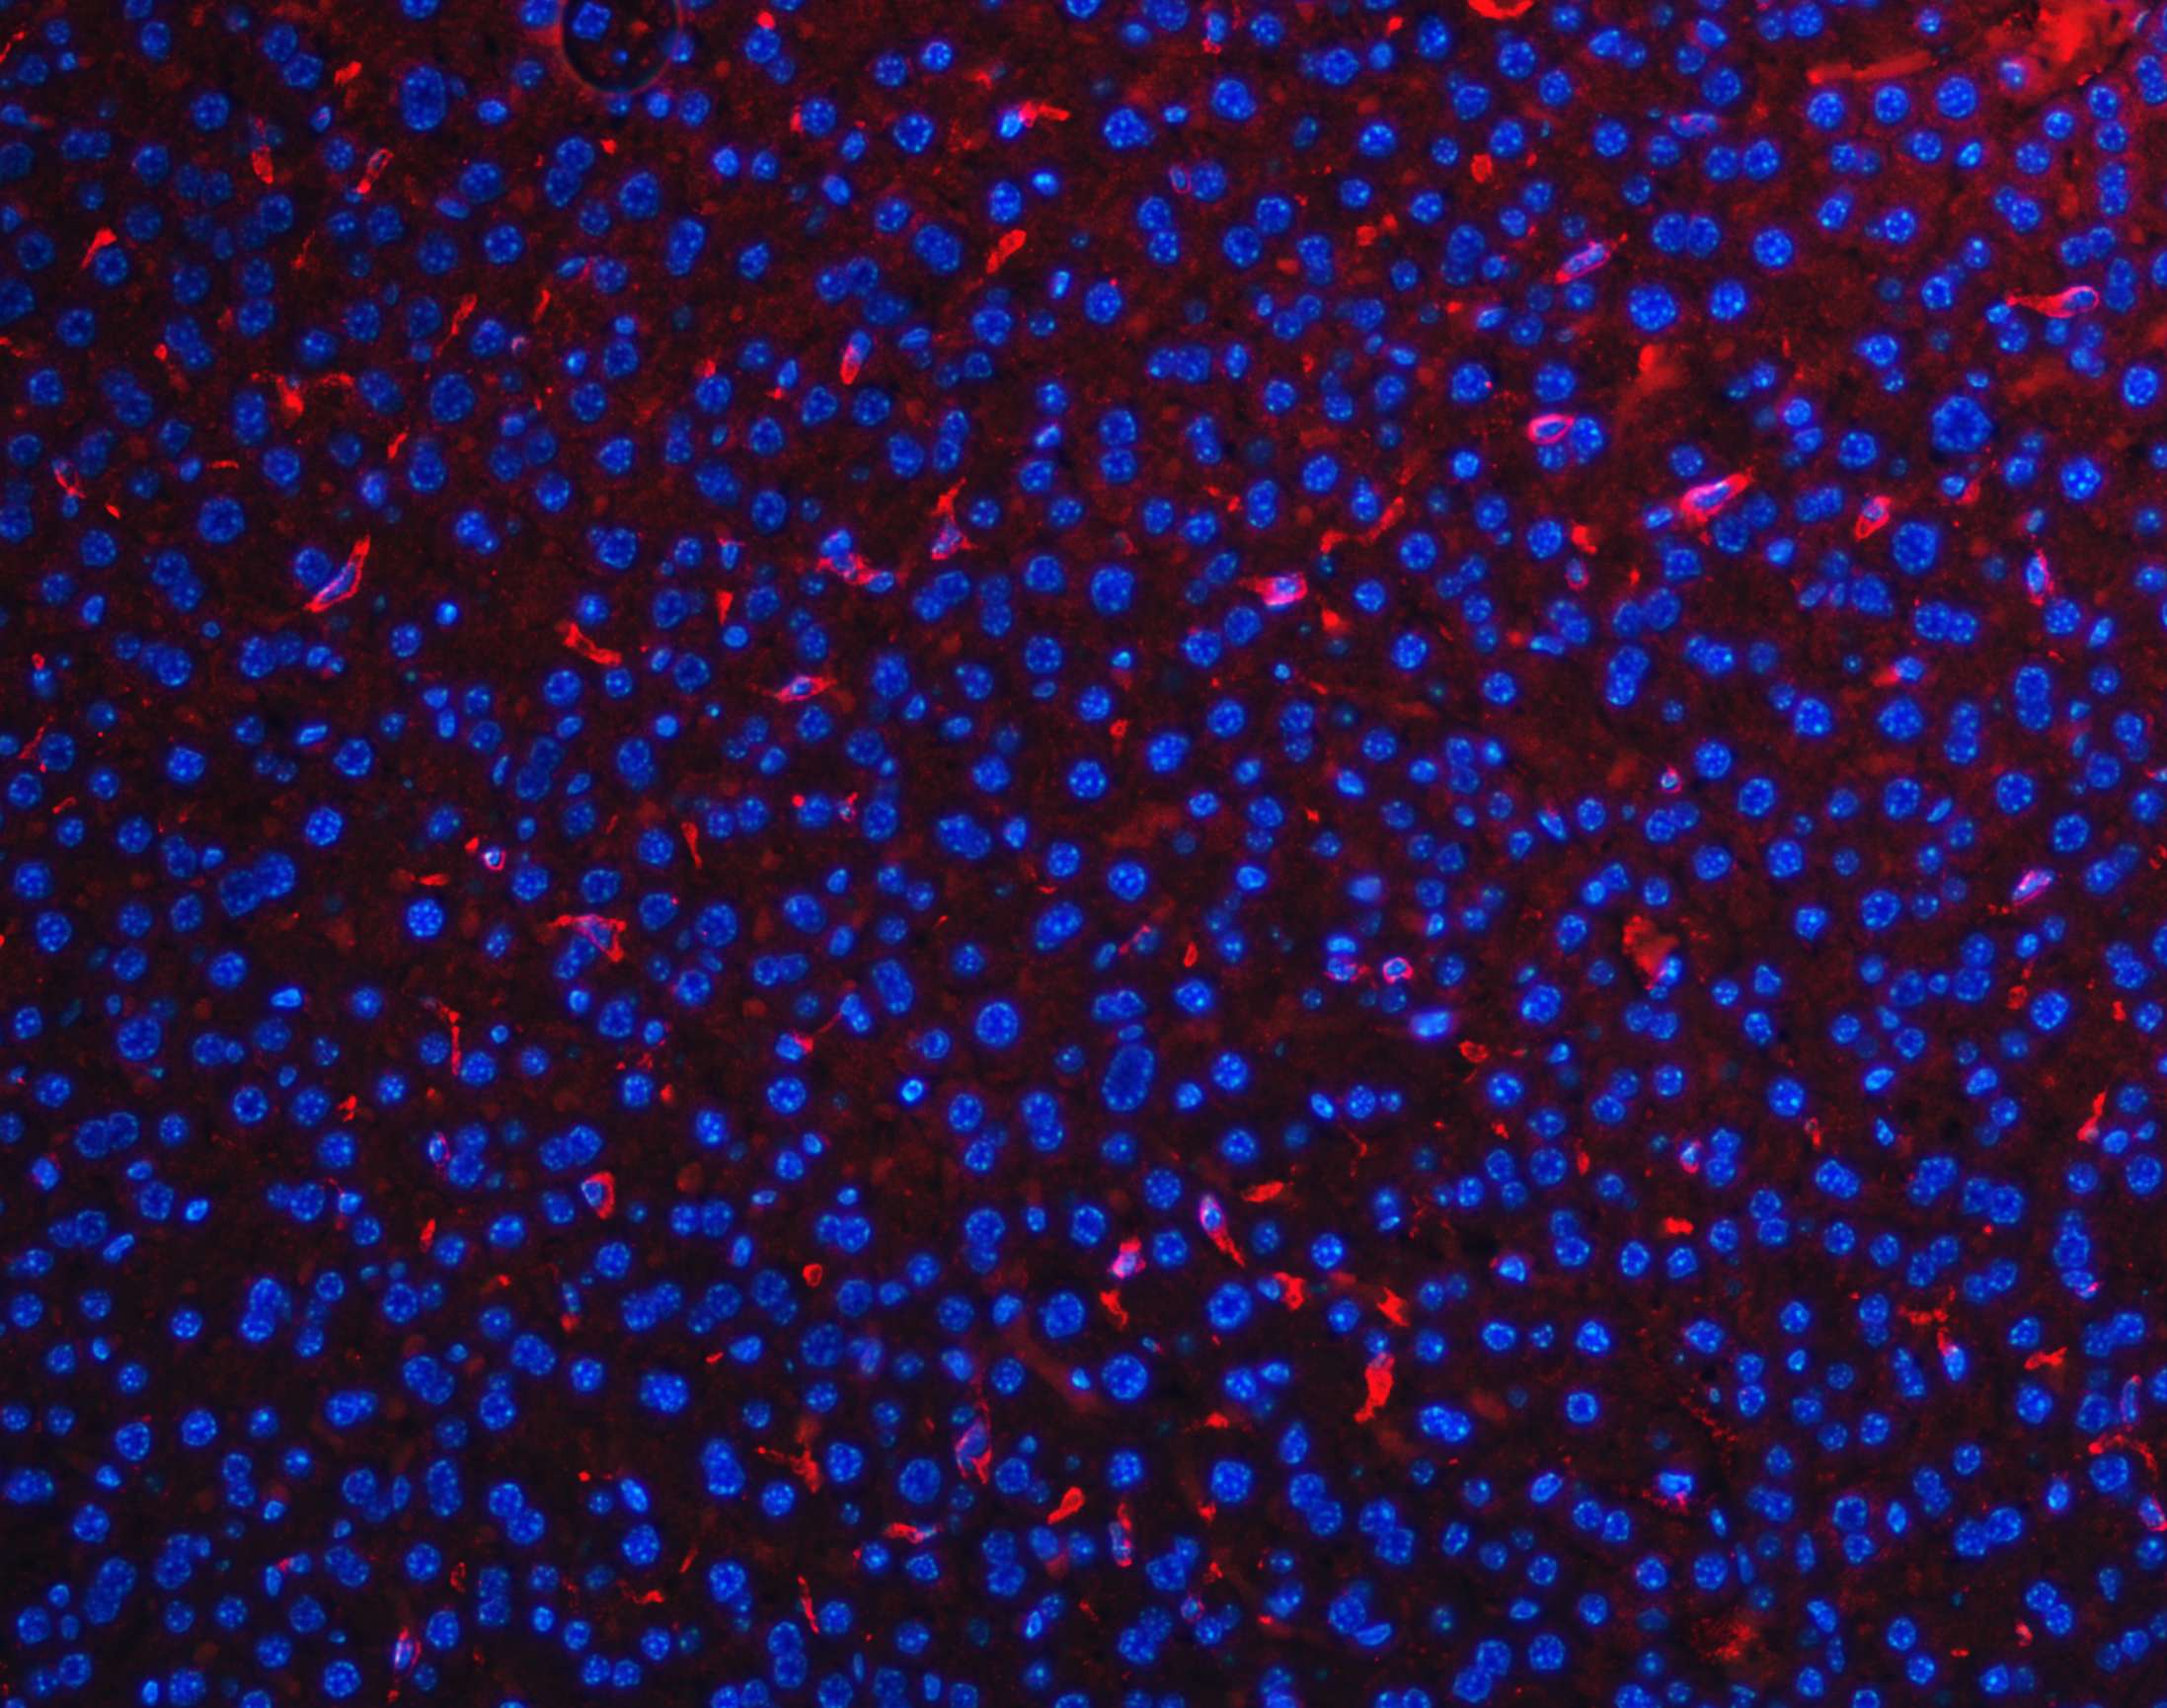

IF analysis of F4/80/Adgre1 using anti-F4/80/Adgre1 antibody (A08751).

F4/80/Adgre1 was detected in a paraffin-embedded section of mouse liver tissue. Cy3-conjugated Anti-rabbit IgG Secondary Antibody (red)(Catalog#BA1032) was used as secondary antibody. The section was counterstained with DAPI (Catalog # AR1176) (Blue).